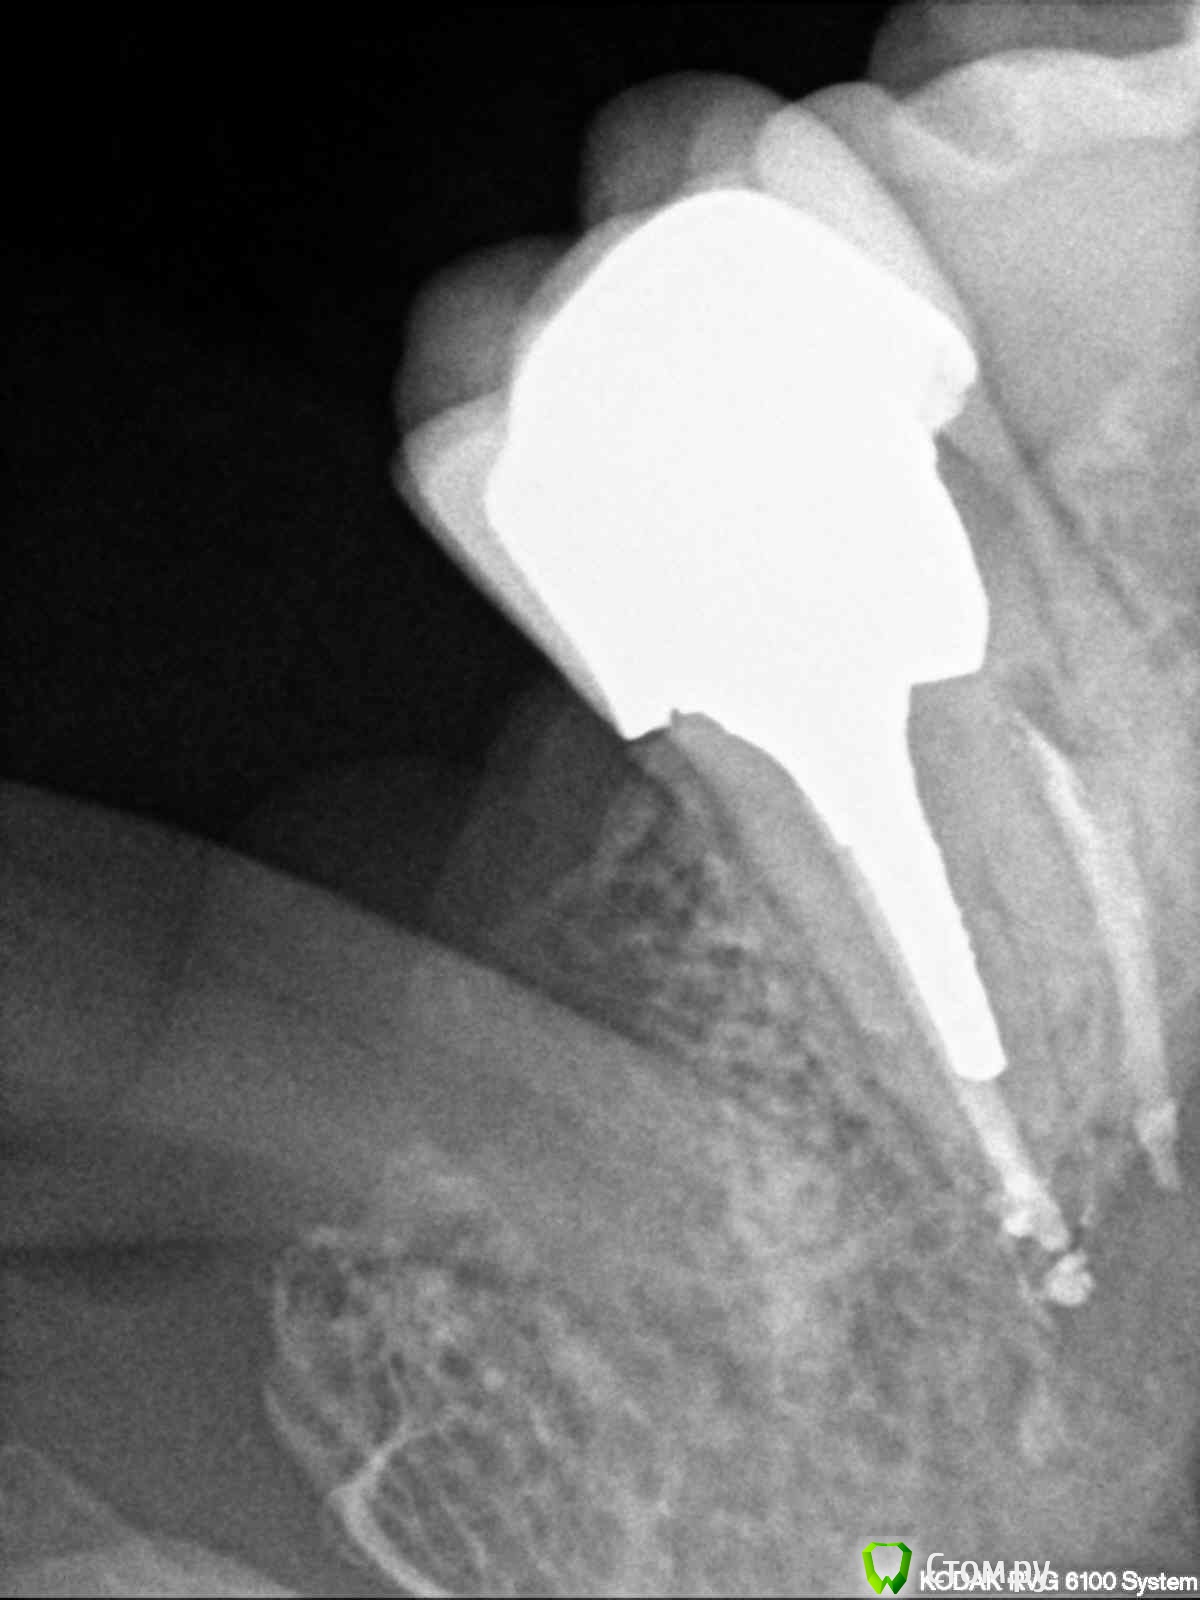

englishlady Опубликовано 12 марта, 2014 Поделиться Опубликовано 12 марта, 2014 Уважаемые врачи, здравствуйте.Существет 27 зуб, на который летом была установлена коронка. Начиная с ноября-декабря, область десны вокруг зуба стала ныть, при чистке зубов десна в этом месте тоже более болезненна, периодически этот зуб отдает в скулу и пазуху. Но эти ощущения не очень сильные, периодически проходят, обезболивающие я пока не принимаю.На ряде форумов мне сказали, что у этого зуба периодонтит, что перелечивать его бесполезно. Может помочь только резекция или имплантация. Но когда я прихожу на прием в разные клиники, то врачи не видят проблем, поскольку зуб не реагирует ни на холод, ни на перкуссию. Я выкладываю прицельные снимки Есть несколько вопросов:1) насколько будет результативна резекция, если она нужна?2) если лечить его бесполезно, то при имплантации какой понадобится синуслифтинг?3) какой из хирургических вариантов предпочтительнее? На одном форуме врач сказал, что резекция в моем случае плохой вариант, поскольку у меня слишком близко расположена пазуха.4) возможно ли его просто перелечить (например с использованием микроскопа).Заранее спасибо за ваши ответы Ссылка на комментарий

Mane Опубликовано 14 марта, 2014 Поделиться Опубликовано 14 марта, 2014 описанные вами симптомы скорее всего говорят об обострении хронического периодонтита в области 27. резекцию корня делать не нужно - уж слишком безрезультативна эта операция. Но в вашем случае кроме того она может быть еще и нереализуема технически - чтоб судить о том можно ли ее реализовать нужна КТ. но я в этом не вижу смысла. так как все равно бы делать резекцию не стал. так как рано или поздно зуб придется удалить (уже после резекции). попытаться перелечить у грамотного эндодонтиста - вот это рабочий вариант. но судить о рацинальности такого перелечивания опять нужно по КТ. если зуб на удаление - то ДА, вам понадобится синус - лифтинг в случае имплантации. при желании все можно сделать за одну процедуру - удаление и синус - лифтинг с имплантацией. но опять же. судить о том чтоб все за раз можно только по КТ. вывод - делайте КТ и снимки в студию! Ссылка на комментарий

Mane Опубликовано 20 марта, 2014 Поделиться Опубликовано 20 марта, 2014 Скорее всего стоит. Но окончательно ясно станет после снятия коронки. Ссылка на комментарий